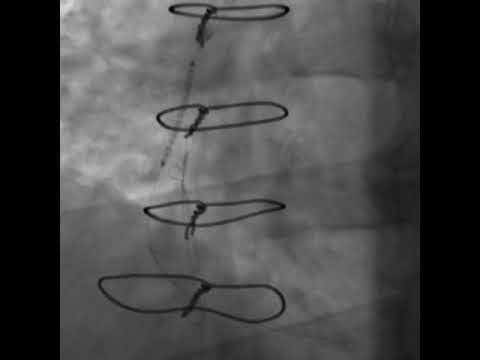

Hellow guys, Welcome to my website, and you are watching Great saphenous vein graft #mbbs #surgeon #rims. and this vIdeo is uploaded by DR SOURABH NEUROSURGEON at 2022-11-29T20:17:47-08:00. We are pramote this video only for entertainment and educational perpose only. So, I hop you like our website.